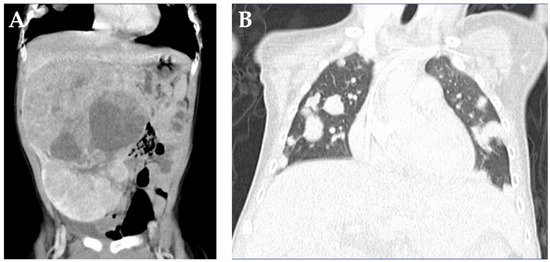

- von Schweinitz, D. Hepatoblastoma: Recent developments in research and treatment. Semin. Pediatr. Surg. 2012, 21, 21–30. [Google Scholar] [CrossRef] [PubMed]

- Hiyama, E.; Hishiki, T.; Watanabe, K.; Ida, K.; Ueda, Y.; Kurihara, S.; Yano, M.; Hoshino, K.; Yokoi, A.; Takama, Y.; et al. Outcome and Late Complications of Hepatoblastomas Treated Using the Japanese Study Group for Pediatric Liver Tumor 2 Protocol. J. Clin. Oncol. 2020, 38, 2488–2498. [Google Scholar] [CrossRef] [PubMed]

- Hishiki, T.; Watanabe, K.; Ida, K.; Hoshino, K.; Iehara, T.; Aoki, Y.; Kazama, T.; Kihira, K.; Takama, Y.; Taguchi, T.; et al. The role of pulmonary metastasectomy for hepatoblastoma in children with metastasis at diagnosis: Results from the JPLT-2 study. J. Pediatr. Surg. 2017, 52, 2051–2055. [Google Scholar] [CrossRef] [PubMed]

- Zsiros, J.; Brugieres, L.; Brock, P.; Roebuck, D.; Maibach, R.; Zimmermann, A.; Childs, M.; Pariente, D.; Laithier, V.; Otte, J.B.; et al. Dose-dense cisplatin-based chemotherapy and surgery for children with high-risk hepatoblastoma (SIOPEL-4): A prospective, single-arm, feasibility study. Lancet Oncol. 2013, 14, 834–842. [Google Scholar] [CrossRef] [Green Version]

- O’Neill, A.F.; Towbin, A.J.; Krailo, M.D.; Xia, C.; Gao, Y.; McCarville, M.B.; Meyers, R.L.; McGahren, E.D.; Tiao, G.M.; Dunn, S.P.; et al. Characterization of Pulmonary Metastases in Children With Hepatoblastoma Treated on Children’s Oncology Group Protocol AHEP0731 (The Treatment of Children With All Stages of Hepatoblastoma): A Report From the Children’s Oncology Group. J. Clin. Oncol. 2017, 35, 3465–3473. [Google Scholar] [CrossRef] [PubMed]